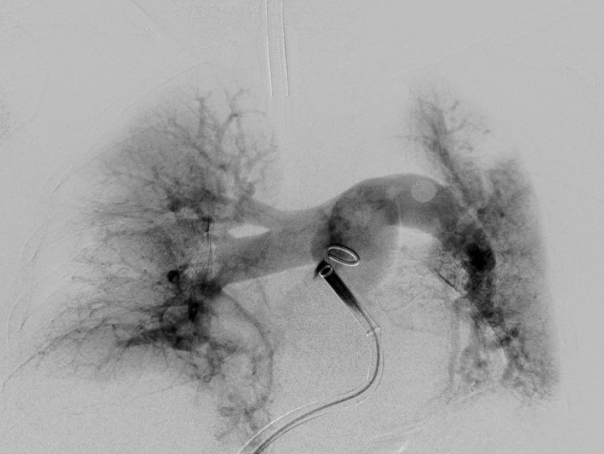

术前造影

导丝导管配合超选进入右肺动脉分支远端,交换硬导丝,更换腾复肺动脉取栓导管,通过负压抽吸取除大部分右肺动脉血栓,同法行左肺动脉取栓,再次造影显示双肺动脉主干血流通畅,远端分支显影可。拔除导丝导管及鞘管,右股静脉压迫包扎手术结束,患者送ICU。术中失血约300ml。

取栓中

术后造影